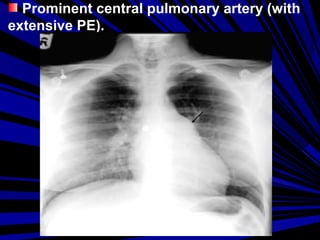

Prominent central pulmonary artery (with

extensive PE).